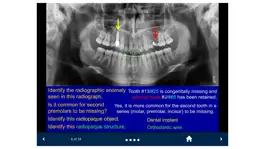

The SecondLook™ Oral Radiology mobile app will help learners of the dental sciences to self-test their level of knowledge and ability to recognize technical errors, anatomical structures, dental disease, and maxillofacial pathology in intraoral and panoramic radiographs, as well as CBCT scans. This app covers the following topics: Radiographic Anatomy (on Periapical & Bitewing Radiographs); Radiographic Anatomy (on Panoramic Radiographs); Image Quality and Common Errors; Radiographic Interpretation; Radiographic Anomalies; Buccal Object Rule (BOR); Cone Beam Computed Tomography (CBCT); Pediatric Radiology; and Presentations of Oral Pathologies (including inflammatory lesions, cyst and cyst-like lesions, benign tumors of the jaws, malignant diseases, bone and systemic diseases).